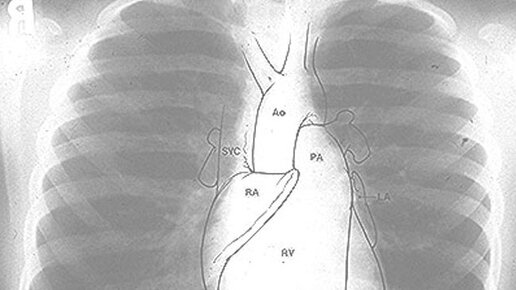

- Вас что привело к кардиологу? - Боли в сердце. - Почему Вы решили, что это болит именно сердце? - Ну как же? Слева болит, вот тут! — пациент тычет пальцем куда-то в область левого соска. И он не одинок в своем заблуждении, будто сердце располагается именно там. Плюс к тому, давно уже выяснилось, что далеко не всегда бывает надежным суждение, что «где болит, там и находится источник боли». Но где же находится сердце? Неужто не слева? Слева, но это верно лишь отчасти. Ибо на одну треть оно находится и справа...

К нам обратилась подписчица Елена. Её беспокоит боль в области сердца. Что это – невралгия или болезнь самого сердца? Мы попросили нашего эксперта рассказать, чем отличается истинная боль в сердце от других болей и тем самым помочь сориентироваться Елене в дальнейших действиях. Надеемся, что ответы на свои вопросы получат и другие наши читатели. Слово – врачу-кардиологу с 20-летним стажем, врачу функциональной диагностики московскому доктору Михаилу НИКОНОВУ: Сердце болит ровно за грудиной по центру Истинная сердечная боль имеет вид давящих, сжимающих, жгучих болей за грудиной...